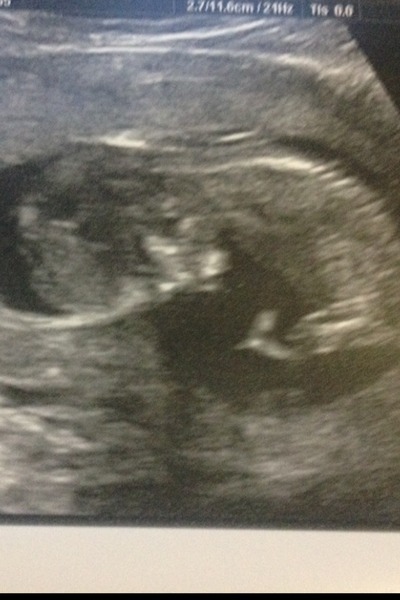

Scan pic, due date altered from 21/06 to 24/06, NT measurements are mid-risk at the moment but obviously need to wait for blood results.

Lovely pic, Elizabeth